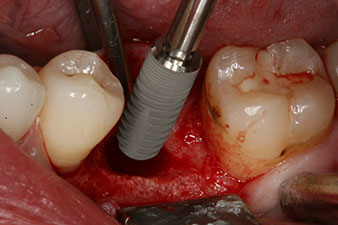

Имплант

Фиг. 3: След препарация с имплантологичния мотор Implantmed, е поставен имплант (диаметър 4 mm, дължина 12 mm) при въртящ момент от 43 Ncm.

Имплантът е поставен както е планирано след цялостно отстраняване на гранулационната тъкан (blueSky, bredent).